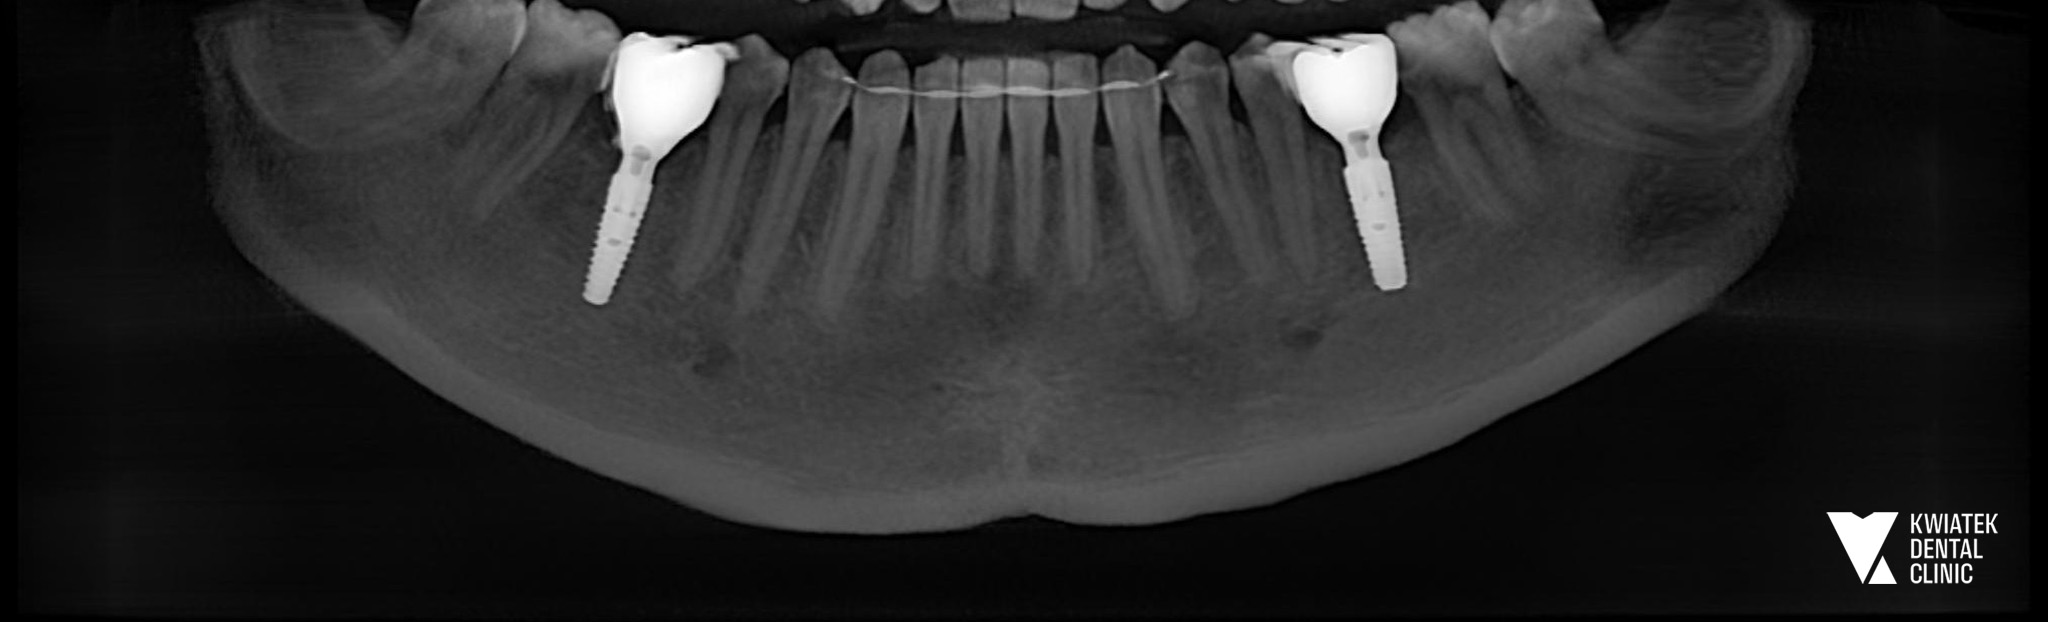

PO

Zabieg implantologiczny został przeprowadzony zgodnie z wcześniej przygotowanym planem. W trakcie procedury zastosowano nowoczesny system implantologiczny MIS C1. W pierwszym etapie wykonano augmentację kości z wykorzystaniem materiału kościozastępczego Bio-Oss oraz kości własnej Pacjentki, co pozwoliło na optymalne przygotowanie podłoża kostnego pod implanty. Następnie wszczepiono dwa implanty w znieczuleniu miejscowym przy użyciu szablonu chirurgicznego, co zapewniło maksymalną precyzję pozycjonowania implantów. W trakcie zabiegu wykonano również śródzabiegową kontrolę radiologiczną RVG oraz badanie CBCT żuchwy. W tym przypadku po implantacji założono śruby gojące, a tkanki miękkie zabezpieczono szwami chirurgicznymi. Pacjentce przekazano szczegółowe zalecenia pozabiegowe oraz wdrożono odpowiednie leczenie farmakologiczne.

Po okresie osteointegracji przeprowadzono etap protetyczny. Wykonano cyfrowe skanowanie implantów z wykorzystaniem scanpostów oraz dobrano odpowiednie łączniki protetyczne typu Ti-base. Finalnym etapem leczenia było wykonanie i osadzenie pełnoceramicznych koron na implantach w miejscach zębów 36 oraz 46, które zostały precyzyjnie dokręcone i zabezpieczone materiałem kompozytowym.

Dzięki kompleksowemu leczeniu implantologicznemu Pacjentka odzyskała pełną funkcję żucia oraz komfort codziennego funkcjonowania. Odbudowane zęby trzonowe przywróciły prawidłowe warunki zgryzowe i równomierne rozłożenie sił podczas żucia.

Zastosowane korony ceramiczne zapewniają naturalną estetykę oraz wysoką trwałość rekonstrukcji. Regularne wizyty kontrolne pozwalają monitorować stabilność pracy protetycznej i utrzymać doskonały efekt leczenia przez wiele lat. Ta metamorfoza jest doskonałym przykładem tego, jak nowoczesna implantologia pozwala w sposób przewidywalny, bezpieczny i estetyczny odbudować utracone zęby oraz przywrócić Pacjentom komfort życia.